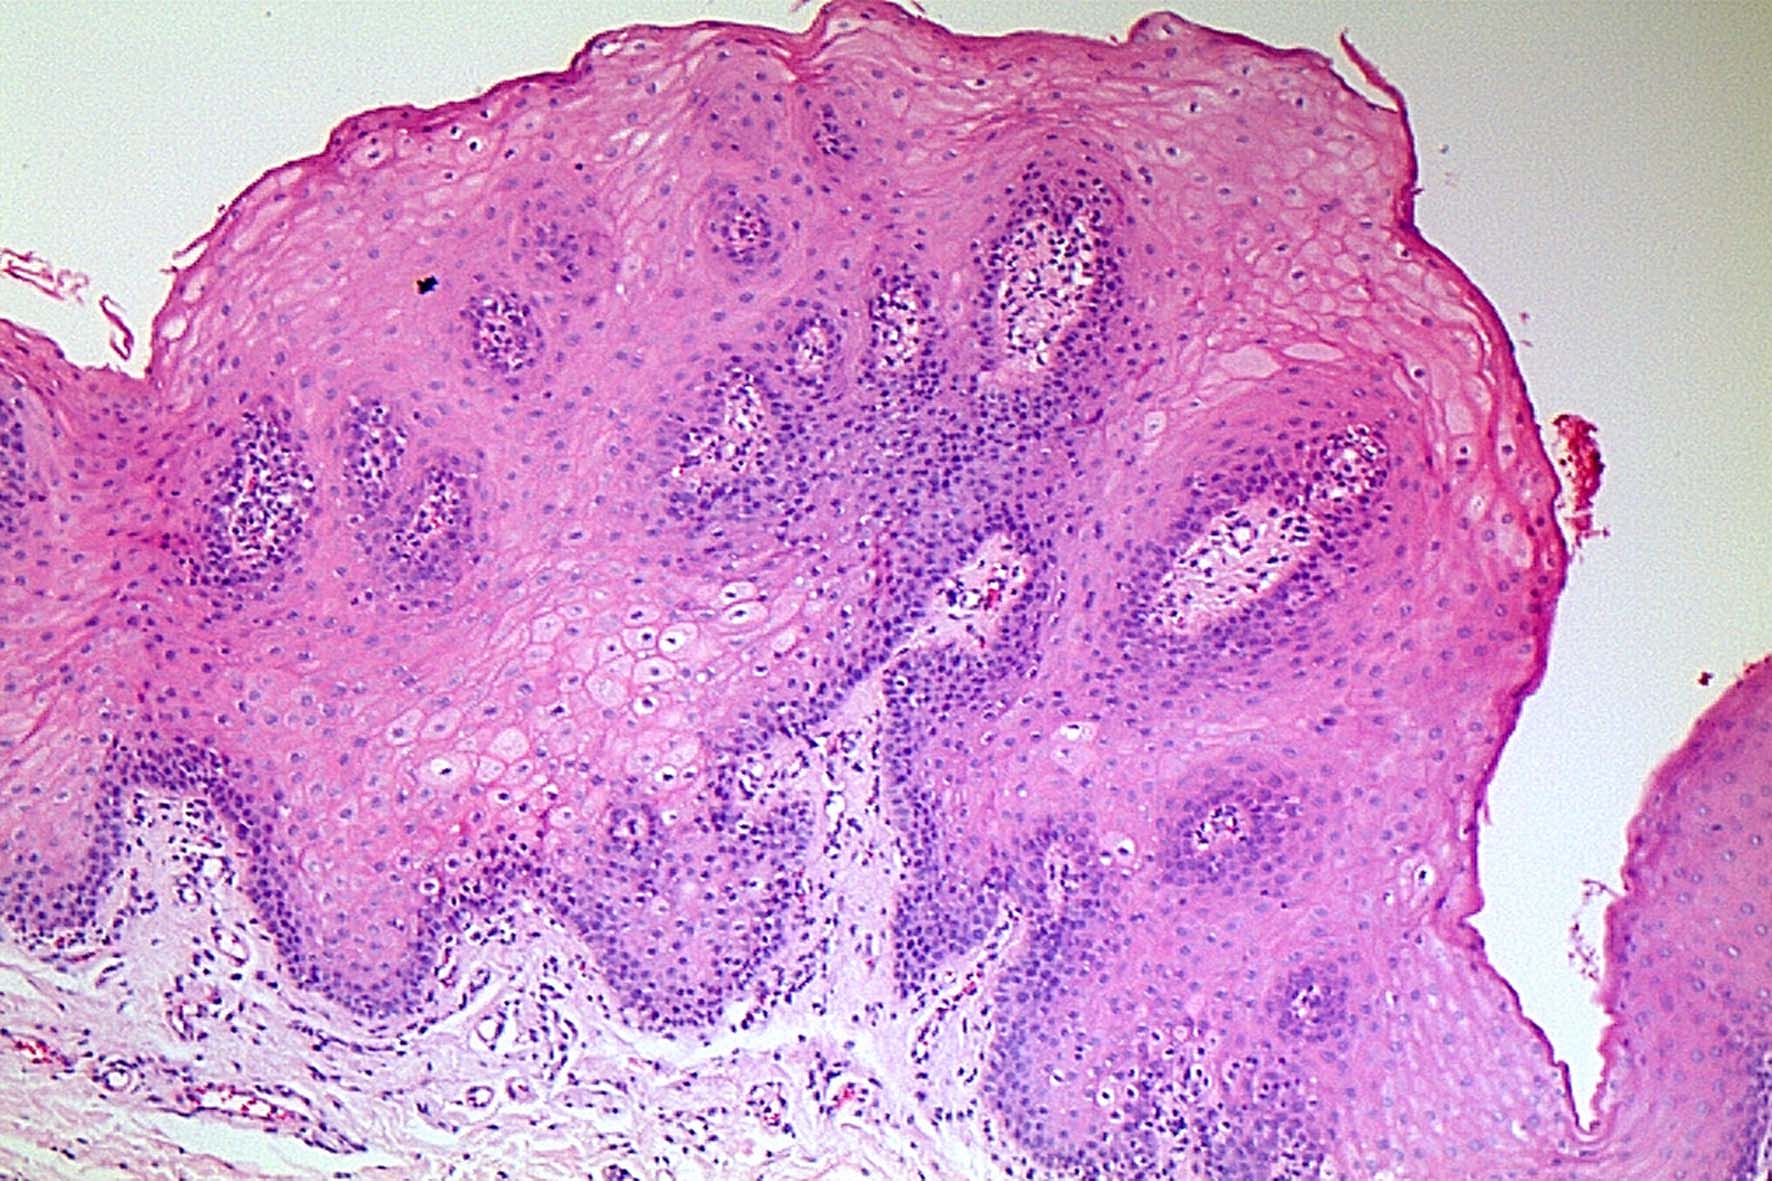

- Figure 5 - Microphotograph (10x) of histological sections stained by hematoxilin-eosin showing the epithelial hyperplasia, acanthosis and inflammatory infiltrate.